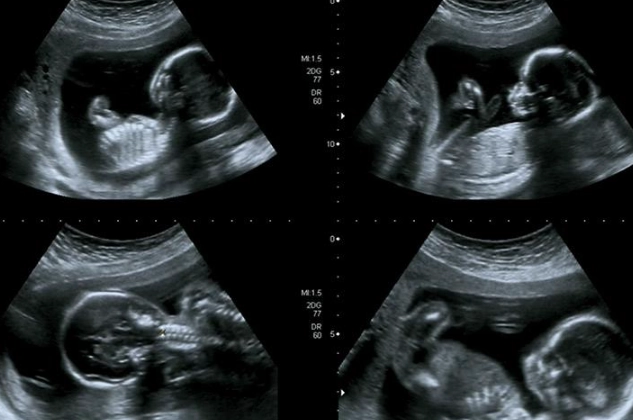

But here's the crucial part everyone misses: On an early ultrasound (usually done at 6-8 weeks to confirm viability), the doctor doesn't just measure the embryo. They measure the gestational sac that contains it and the yolk sac that nourishes it. At 5-6 weeks, you might see the gestational sac measuring 5-10 mm, and a tiny flicker of a heartbeat within the tiny embryo. So when you hear "it's the size of a pea," they're often talking about the whole sac, not the baby itself. The actual embryo is smaller.

Probably not the way you're imagining. At 4 weeks, it's usually too early to see anything conclusive on an abdominal ultrasound. At 5-6 weeks, a transvaginal ultrasound (which provides a closer look) might show the gestational sac and maybe the yolk sac. You might see a tiny, tiny embryo attached to the yolk sac, looking like a little grain of rice. The heartbeat often becomes visible around 6 weeks. Most doctors prefer to wait until 7-8 weeks for the first ultrasound to get clearer, more reassuring measurements and confirm the heartbeat. Going too early can cause unnecessary anxiety if they can't see much yet.